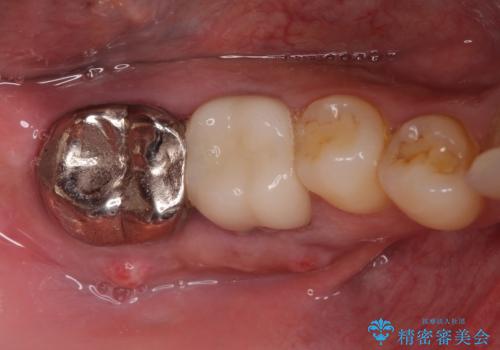

[歯周病治療] 歯周補綴 インプラント補綴

ソケットリフトを伴うインプラント補綴